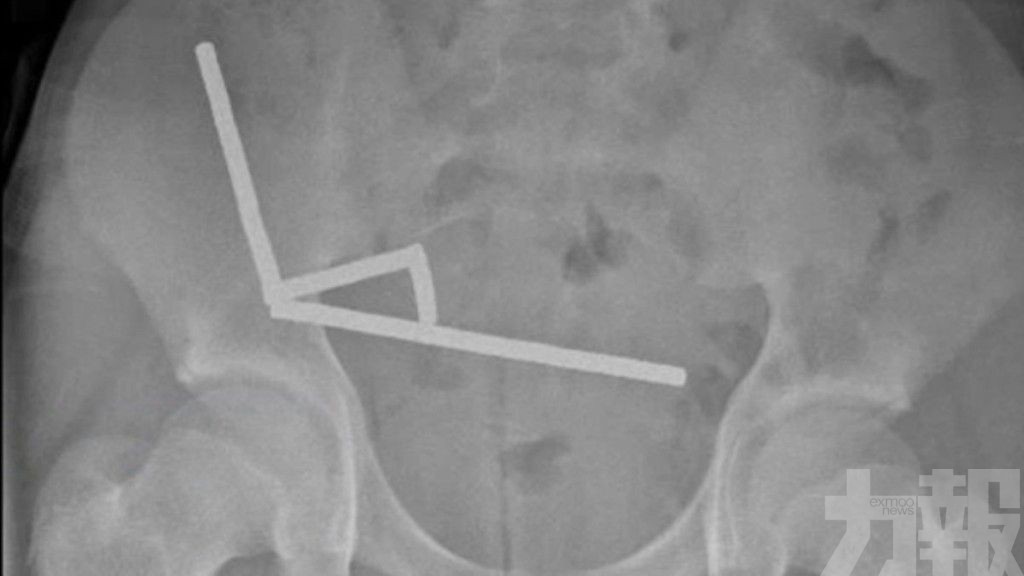

根據《紐西蘭醫學期刊》報導,該名少年腹痛持續4天後,被送往北島陶朗加醫院(Tauranga Hospital)。X光片顯示,多顆磁鐵在腸道不同位置因磁力相吸,形成4條長鏈。醫生發現磁鐵對腸壁造成嚴重壓力,導致小腸與盲腸共有4處組織壞死。